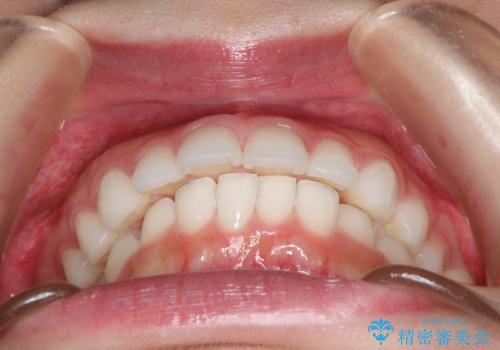

出っ歯の矯正治療 歯を抜かずにインビザラインで

- インビザラインで出っ歯を治したいとの希望がありました。

上顎の歯を全体的に後方に移動させて前歯を引っ込める計画としました。

インビザラインで目立たずに、痛みも少なく矯正治療を終えることができ満足していただけました。